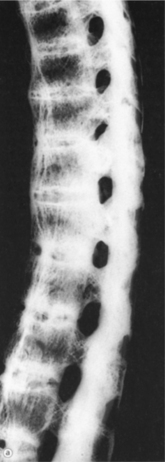

Disruption of this ligamentous-osseous junction results, and reactive bone formation occurs as part of the repair process. Cartilage of the sacroiliac joints may also be involved (Fig. 27-19). The replacement of inflamed cartilaginous structures by bone contributes to progressive ossification with bony growth between the vertebrae, leading to a fused, rigid, or bamboo spine, characteristic of end-stage disease (see Fig. 27-20).

Radiographic findings of symmetric, bilateral sacroiliitis include blurring of joint margins, juxtaarticular sclerosis, erosions, and joint space narrowing. The replacement of ligamentous tissue by bone at the site where the annulus fibrosus of the intervertebral disk inserts into the vertebral body results in a characteristic square-shaped vertebral body. In addition, as bony tissue bridges the vertebral bodies and posterior arches, the thoracic and lumbar spine takes on the appearance of a bamboo spine on radiographs (Fig. 27-20).

Figure 27-20 Radiograph of a sagittal vertebral column in a person with ankylosing spondylitis. There is complete fusion of the spine, accentuated kyphosis, and loss of lumbar and cervical lordosis. There is also complete fusion of the intervertebral disk spaces. (From Bullough PG: Orthopaedic pathology, ed 3, London, 1997, Mosby-Wolfe, p 301.)